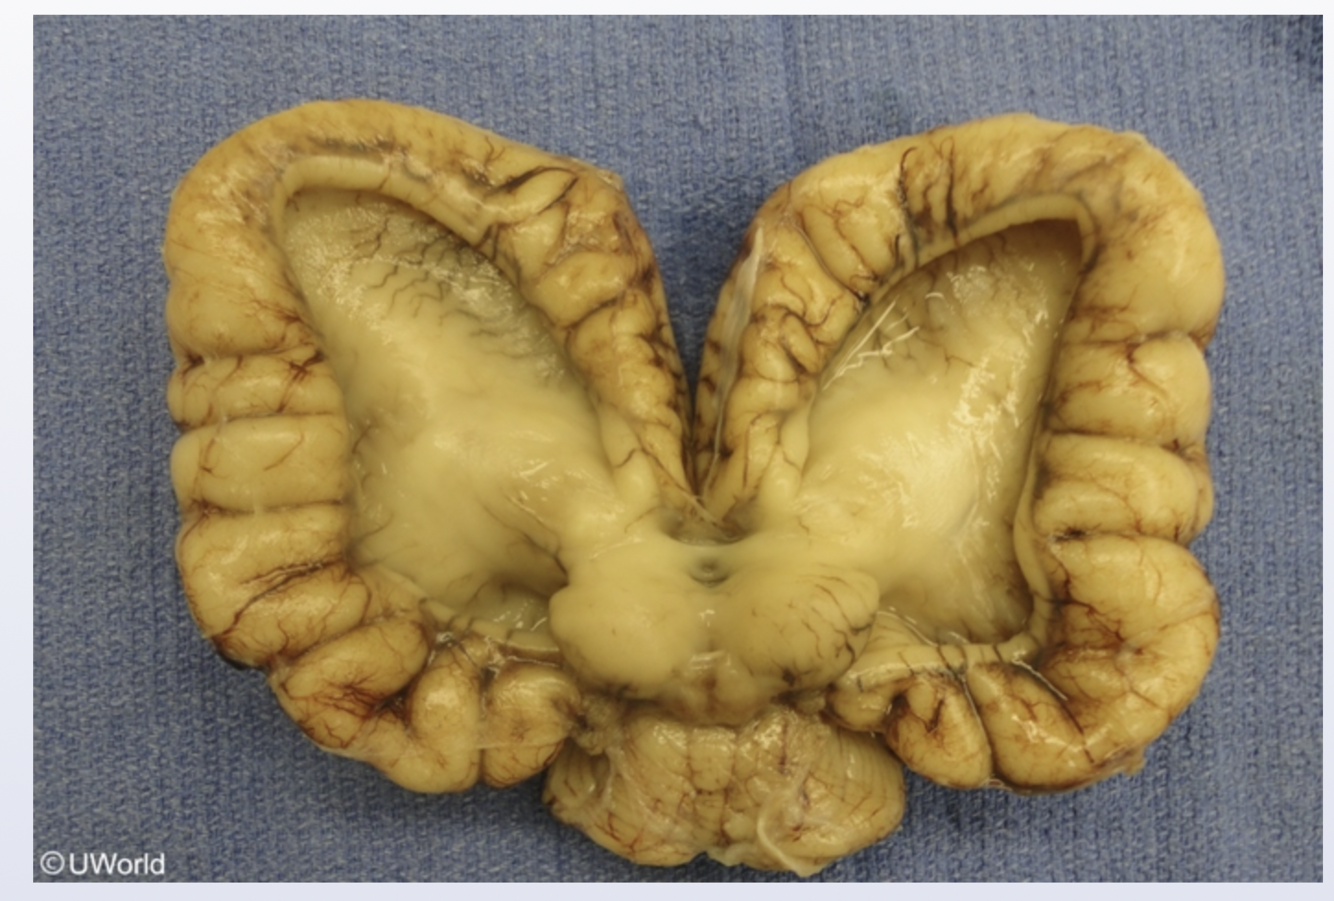

Holoprosencephaly

Holoprosencephaly is due to failure of the primitive forebrain (prosencephalon) to divide into the right and left hemispheres, resulting in a spectrum of brain and mid face abnormalities; trisomy 13 is the most commonly associated etiology